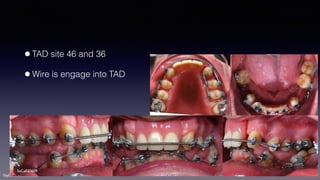

•TAD site 46 and 36

•Wire is engage into TAD

SeCa020609